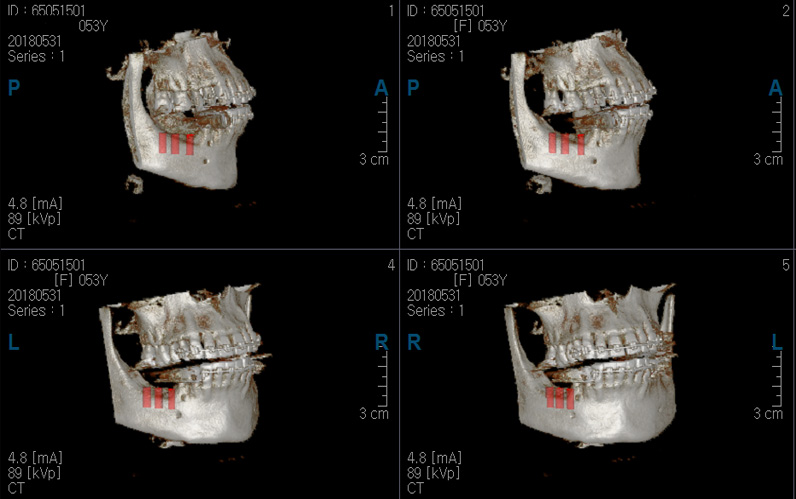

3차원 입체 CT를 이용하여 정확하고 세밀한 검사와 진단을 토대로 안전하고 장기적인 예후가 우수한 임플란트가 해미인치과의 자랑입니다.

정확하고 안전한 임플란트 식립을 위해 3차원 입체 CT 등 첨단 장비 시스템을 구축하고 있습니다. 안전하고 만족스러운 임플란트를 위해서 장비와 시스템 또한 매우 중요합니다. 해미인 치과에서는 3D CT 등 디지탈 장비를 이용하여 임플란트 수술전 simulation 모의 수술을 실시하여 보다 안전하고 만족스러운 결과를 선사합니다.